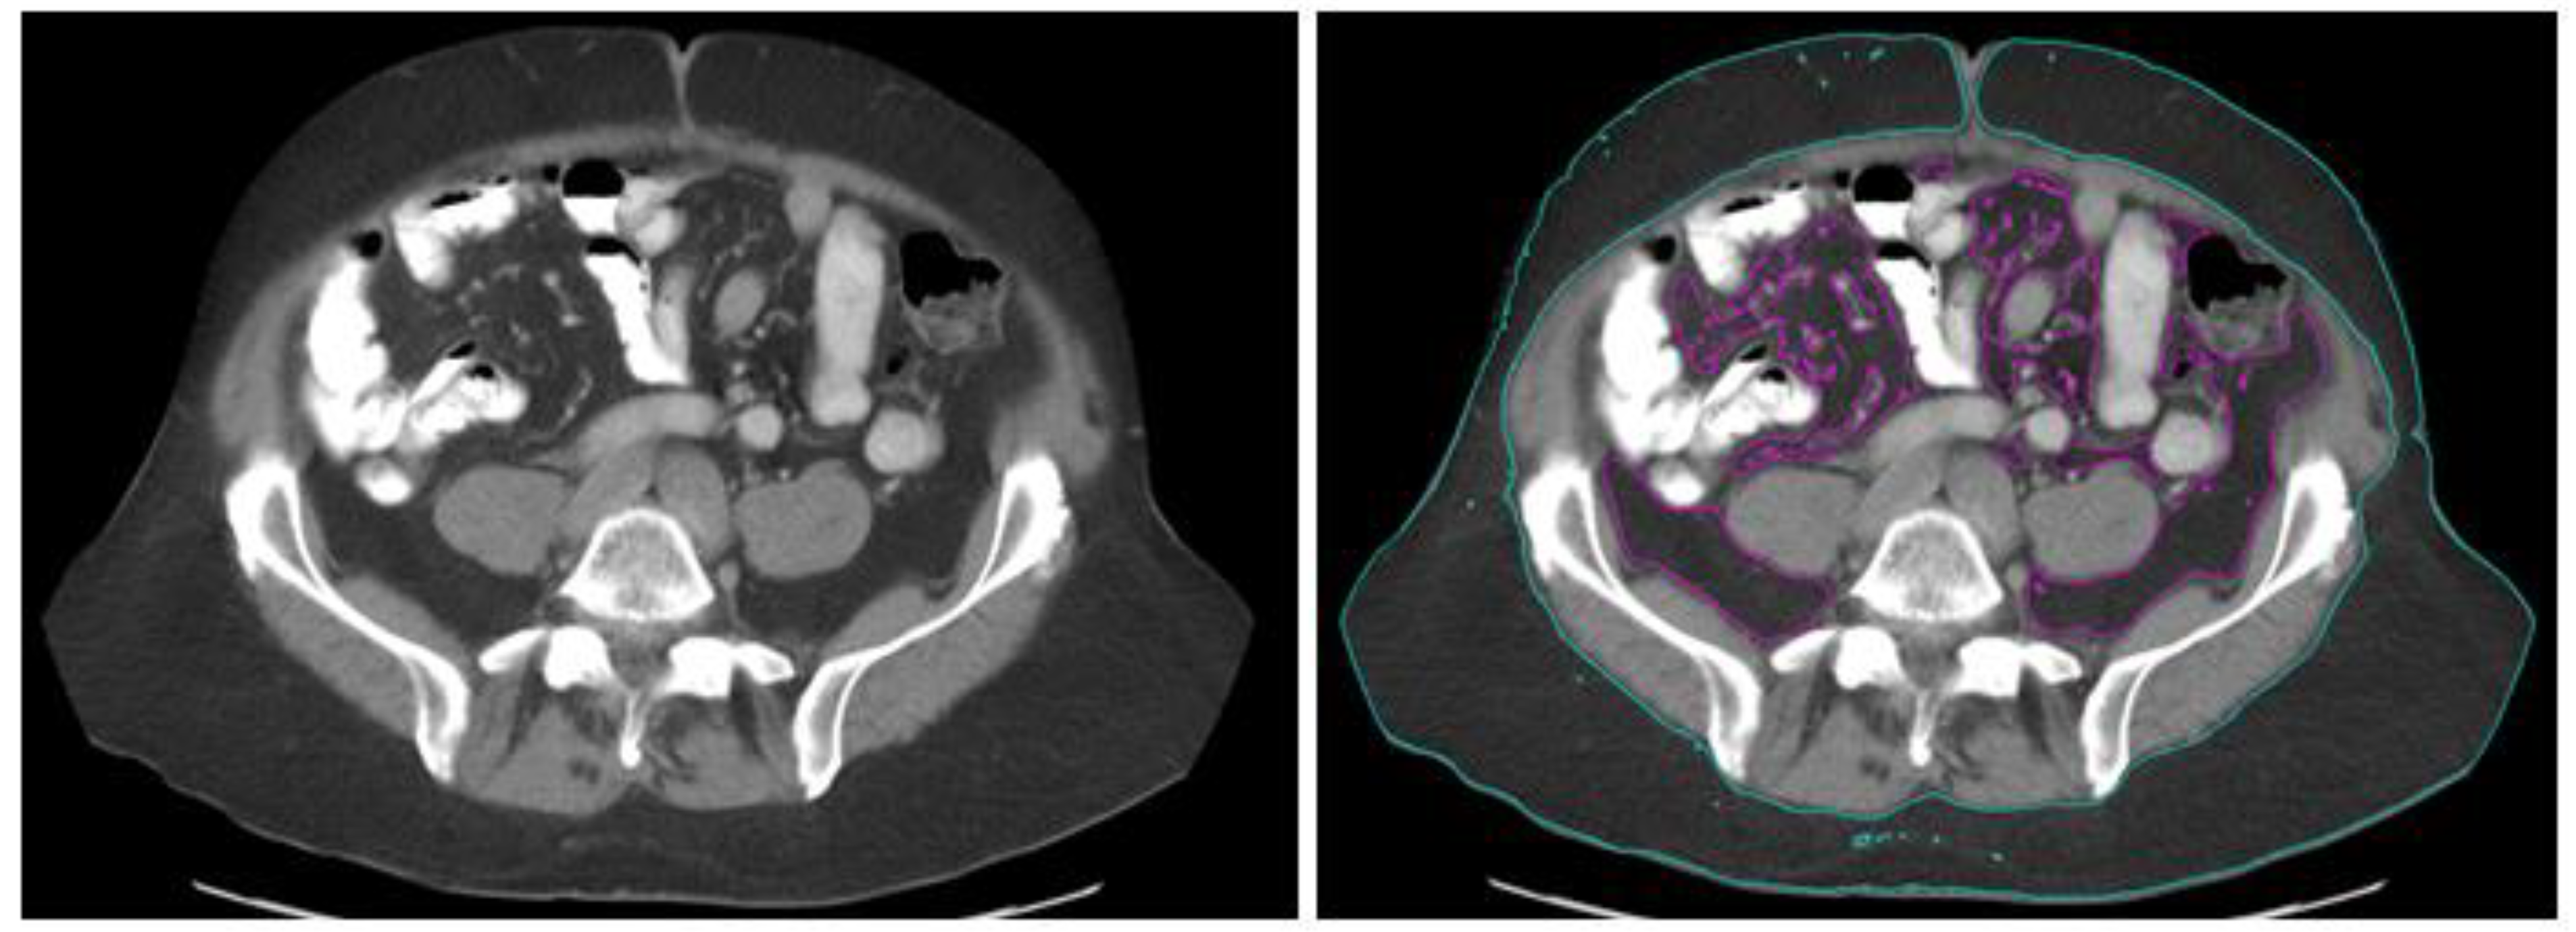

3.4. Correlation between BMI and Visceral Body Fat Parameters

| Parameter | Pearson Correlation Coefficient | p Value |

|---|---|---|

| SFA | 0.635 | <0.0001 |

| VFA | 0.579 | <0.0001 |

| TFA | 0.673 | <0.0001 |

| V/S ratio | 0.115 | 0.105 |